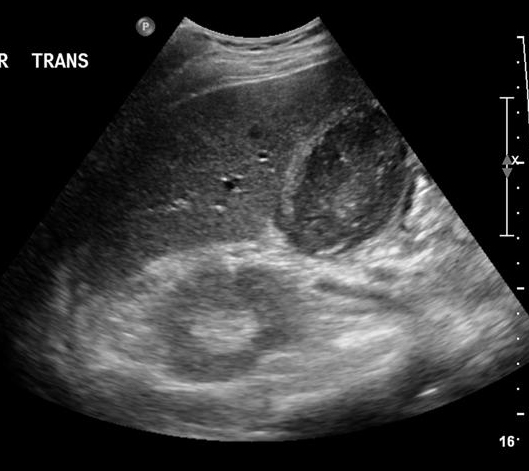

Image echographique de

multiple calcul vesiculaire avec epaissisement de la

paroi vesiculaire tres marquee . Cholecystite aigue

lithiasique |